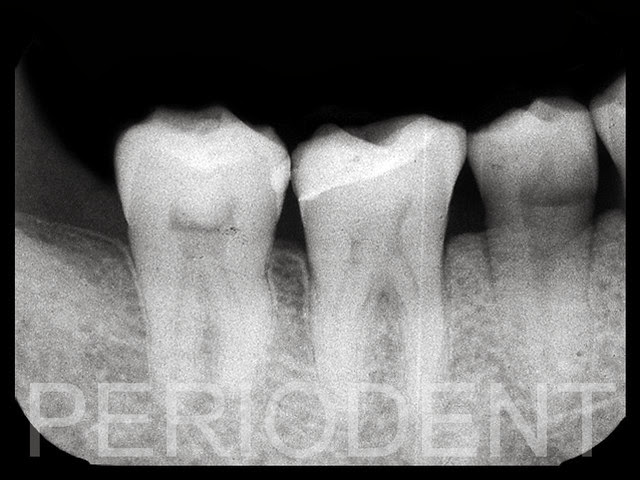

右下第二大臼齒因為右上區缺牙,而有往上移位,

煩請胡兆仁醫師利用矯正治療將牙齒做

Intrusion 。